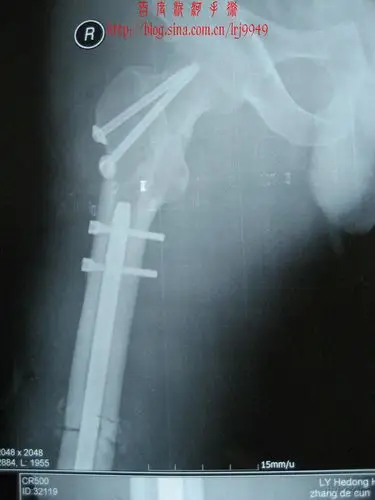

一例少见的股骨骨折